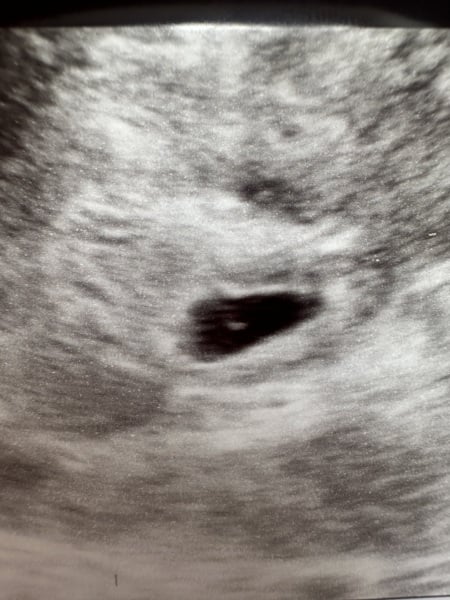

So I went for an early scan today due to bleeding. I’m 5+3 apparently. However once I got home and looked at the picture properly I noticed the little shadow/blob at the top? Does anyone see it? Did anyone have this to later on show two?

fraternal twins do run in the family and I’m older 🤪

Could be shadowing on the scan

Not sure in that one sorry @ADW1985